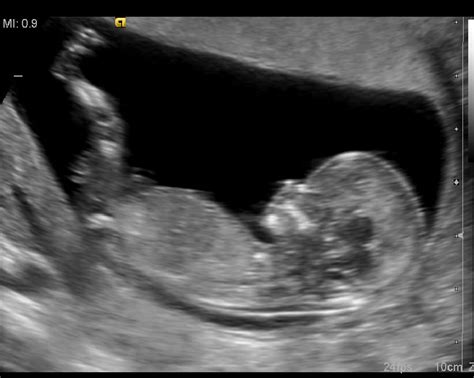

Dojenček stoji pokonci v trebuhu! Divji brcanji in gibanje 38 tednov